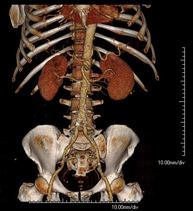

- TC Riñones

Prueba diagnóstica que consiste en obtener imágenes bi y tridimensionales del riñón y del sistema urinario de alta definición anatómica mediante el empleo de un equipo de TC (Tomografía Computarizada). Se realiza el estudio antes y después del empleo de contraste yodado en diferentes "fases renales" para una valoración funcional y anatómica (parénquima renal, uréteres, vejiga urinaria, arterias y venas renales, etc.), así como las estructuras adyacentes (vena cava inferior, aorta abdominal, hígado, bazo, etc.). Está especialmente indicado ante la sospecha de lesiones renales, en pacientes con sangre en orina o hematuria, etc.